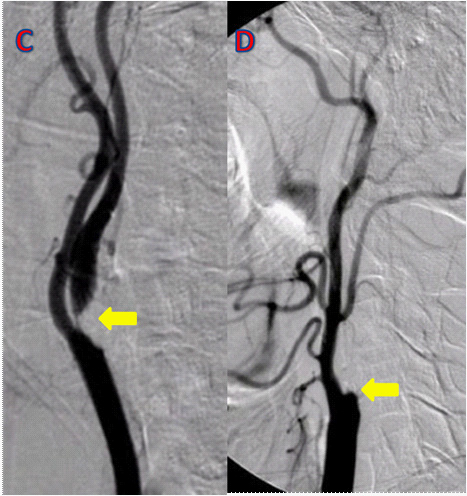

두개강외 경동맥 협착(Extracranial carotid artery stenosis)

• 영상

• 치료

• 유증상의 중증도 내경동맥협착(협착 정도≥50%)

• 경동맥 내막절제술(Carotid endarterectomy)

• 스텐트 설치술(Carotid Artery Stent)으로 대체 가능